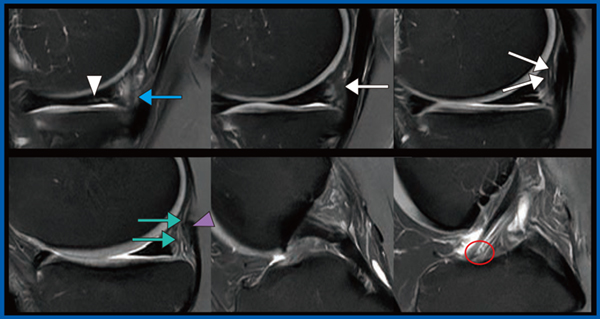

図1は,AiCEを適用した交通外傷症例の膝の画像であるが,内側半月板に断裂(▽)を認めるほか,これまで“don’t touch region”とされてきた前十字靭帯の前内側線維束(anteromedial bundle)遠位部の断裂(○)が,無視できないほど明瞭に描出されている。

また,図1→は後内側支持組織損傷(posteromedial corner injury)である。従来のMR画像では,後内側支持組織損傷は内側半月板後節の腫脹のように描出されるが,AiCEを適用した画像では,後斜走靭帯のsuperficial arm(図1←)とcentral arm(→)の著明な腫脹を分離して評価できるほか,斜膝窩靭帯(◀)も確認でき,これらから後内側支持組織損傷であることを容易に診断できる。

図1 AiCEによるdon’t touch regionの描出